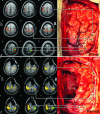

Background and purpose: Resting-state functional MR imaging has been used for motor mapping in presurgical planning but never used intraoperatively. This study aimed to investigate the feasibility of applying intraoperative resting-state functional MR imaging for the safe resection of gliomas using real-time motor cortex mapping during an operation.

Materials and methods: Using interventional MR imaging, we conducted preoperative and intraoperative resting-state intrinsic functional connectivity analyses of the motor cortex in 30 patients with brain tumors. Factors that may influence intraoperative imaging quality, including anesthesia type (general or awake anesthesia) and tumor cavity (filled with normal saline or not), were studied to investigate image quality. Additionally, direct cortical stimulation was used to validate the accuracy of intraoperative resting-state fMRI in mapping the motor cortex.

Results: Preoperative and intraoperative resting-state fMRI scans were acquired for all patients. Fourteen patients who successfully completed both sufficient intraoperative resting-state fMRI and direct cortical stimulation were used for further analysis of sensitivity and specificity. Compared with those subjected to direct cortical stimulation, the sensitivity and specificity of intraoperative resting-state fMRI in localizing the motor area were 61.7% and 93.7%, respectively. The image quality of intraoperative resting-state fMRI was better when the tumor cavity was filled with normal saline (P = .049). However, no significant difference between the anesthesia types was observed (P = .102).

Conclusions: This study demonstrates the feasibility of using intraoperative resting-state fMRI for real-time localization of functional areas during a neurologic operation. The findings suggest that using intraoperative resting-state fMRI can avoid the risk of intraoperative seizures due to direct cortical stimulation and may provide neurosurgeons with valuable information to facilitate the safe resection of gliomas.